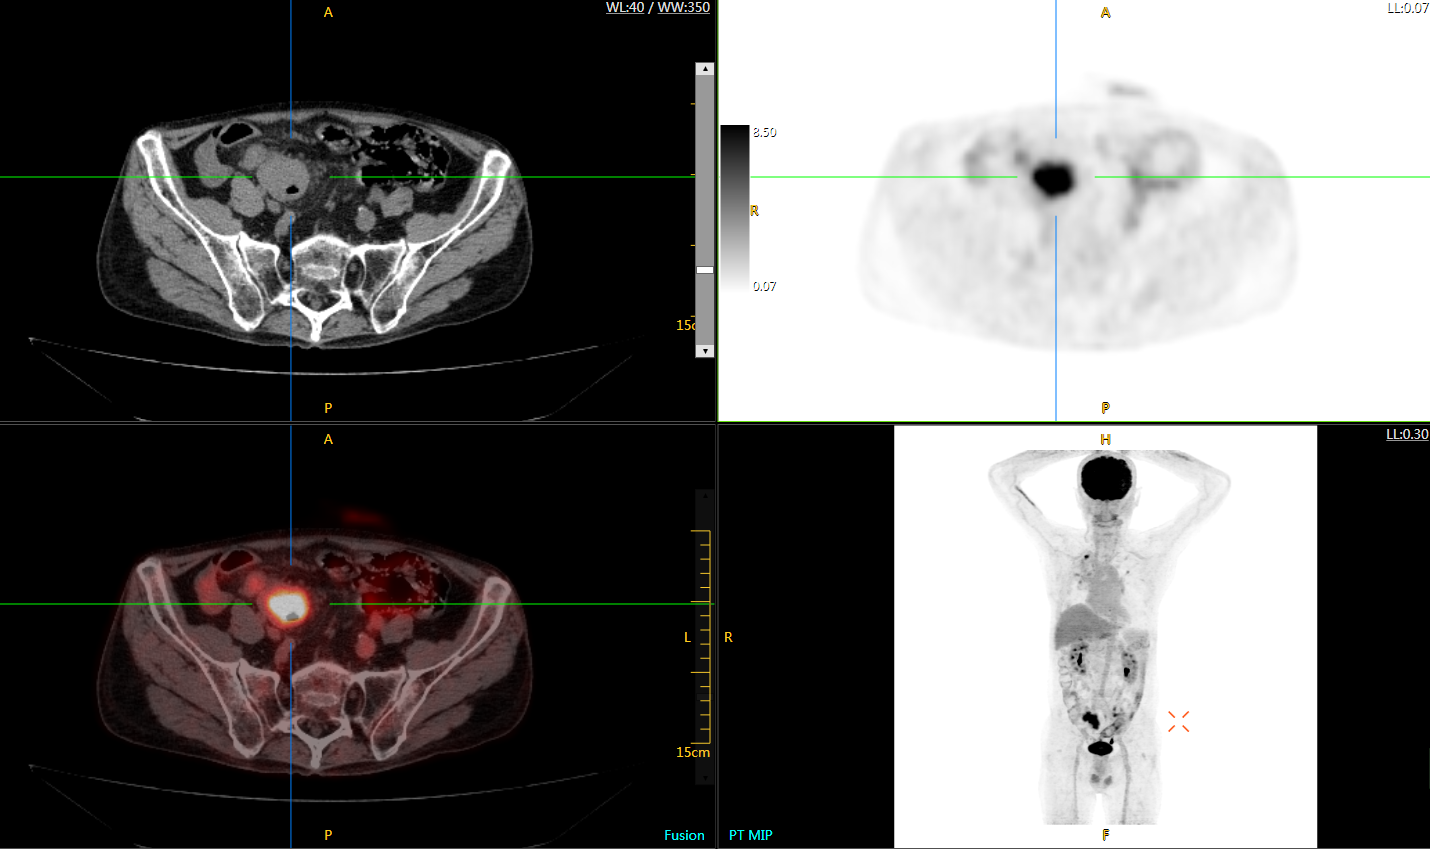

可4D呈現(xiàn)體內(nèi)藥物實(shí)時(shí)代謝情況,讓全身藥效可視化,全方位評(píng)估療效,加速藥物研發(fā);可精準(zhǔn)定位腫瘤位置,監(jiān)控腫瘤微轉(zhuǎn)移,助力定點(diǎn)靶向治療,讓腫瘤無(wú)處可藏;科研探索領(lǐng)域,以代謝信息判斷神經(jīng)膠質(zhì)細(xì)胞變化,讓細(xì)胞“開口說(shuō)話”,助力多器官神經(jīng)關(guān)聯(lián)研究…

uExplorer探索者不再局限于傳統(tǒng)靜態(tài)代謝過程3D成像,而是在此基礎(chǔ)上新增一個(gè)維度——時(shí)間,從而實(shí)現(xiàn)4D全景成像。